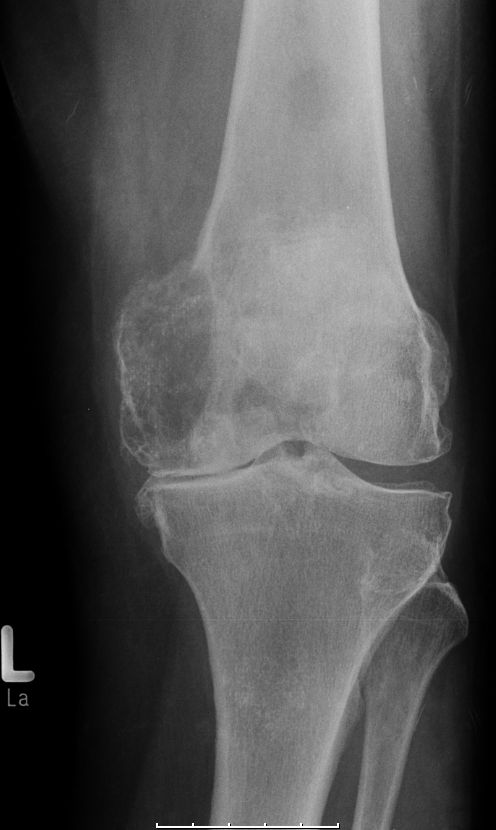

Knie | 83jährige Frau

mit schwerer Gonarthose. Knochenmetastasen als Erstsymptom eines

Mammakarzinoms.![]() | ||||||||||